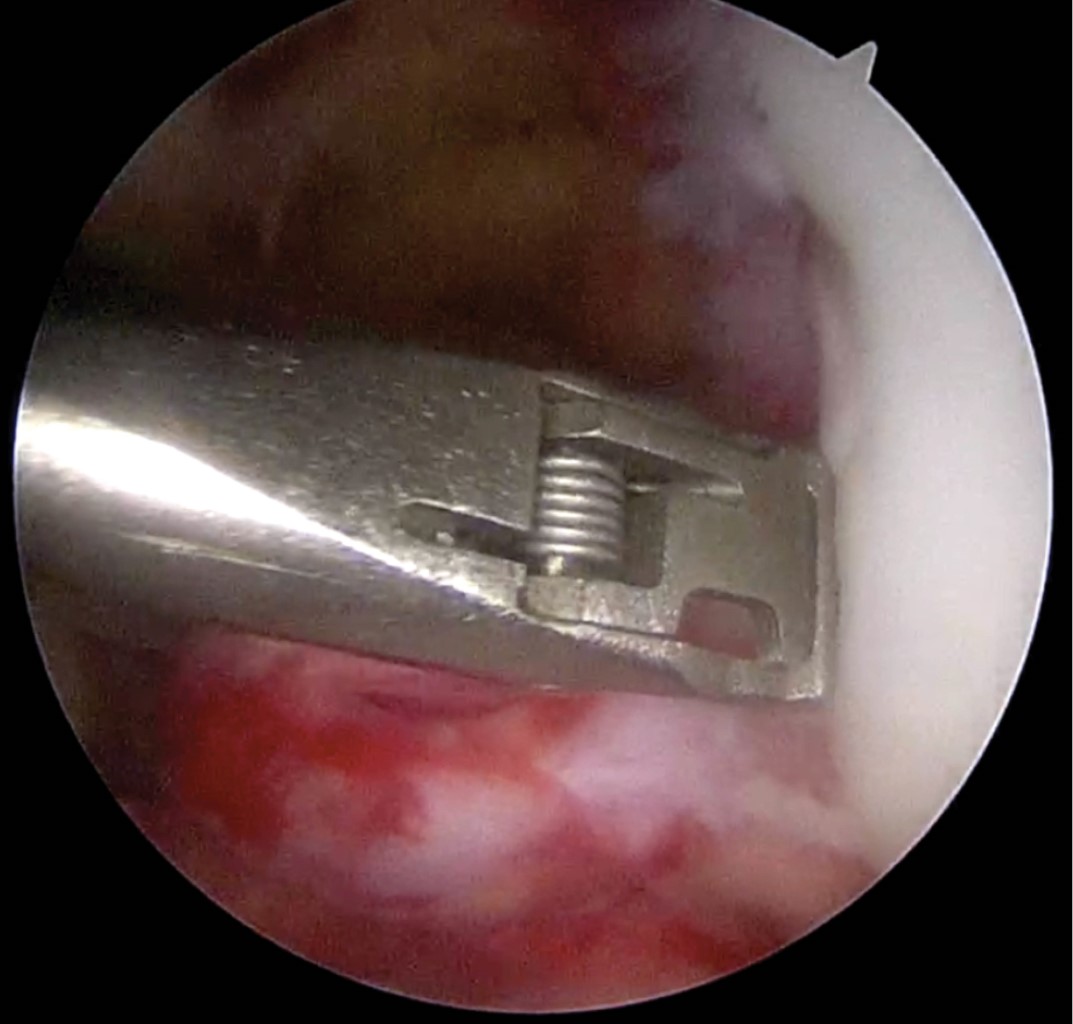

Introduction: Anterior cruciate ligament injuries are common, however, tibial avulsions in adults are rare. The gold standard continues to be reconstruction either by allograft or autologous graft. Primary repairs in femoral side lesions have been reported in recent years by bioabsorbable anchors. Case report: We present the case of a primary repair of anterior cruciate ligament due to tibial avulsion in a patient 19 years after presenting direct trauma with added lesions of posterior cruciate ligament and posterolateral corner. Primary repair was performed by trans-tendon portal with suture of the anterior cruciate ligament crossed by FiberTape and FiberWire with a SwiveLock anchor (4.75 mm) in tibial footprint. Results: Twelve months after surgery is with independent gait, full range of movement, with clinical rating scales, Tegner before injury and post-injury at 6, Lysholm 91, 73.6 subjective IKDC, objective IKDC in C and EQ-5D 0.79. Conclusion: Fixation with bioabsorbable anchor is possible in the avulsion of the post-traumatic tibial spine.

Figure 1